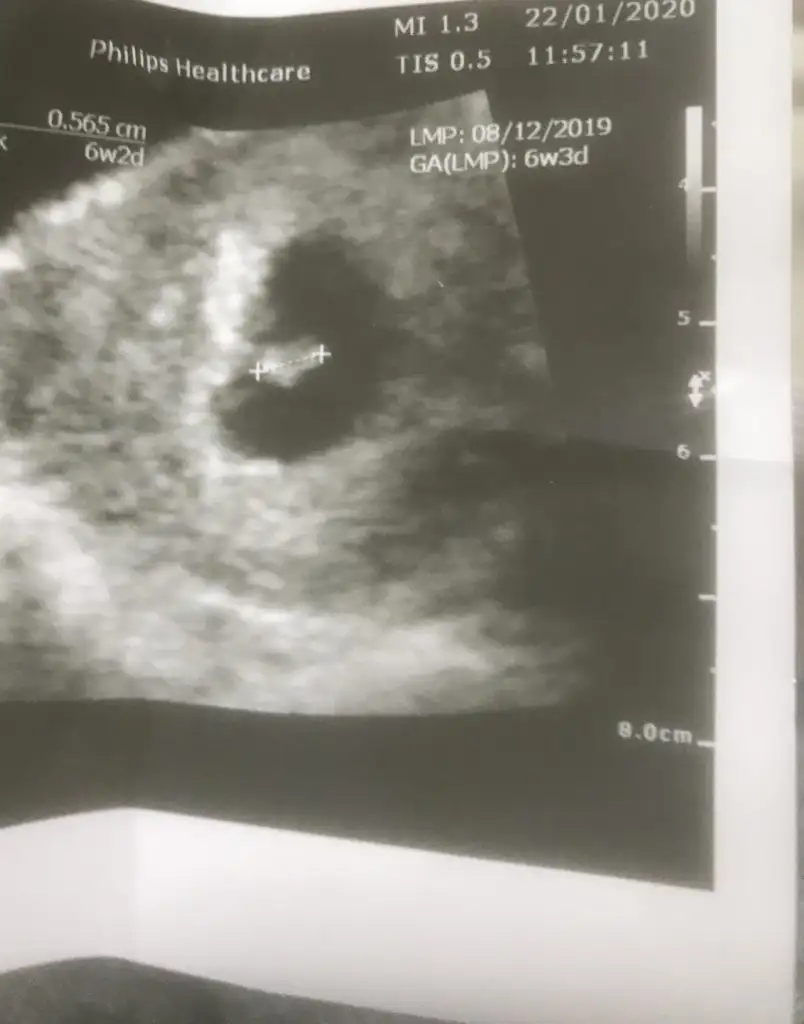

Merhabaa 6+3 karından ultrasonumm cinsiyet tahminii yapabilirmisiiniz🥰

17,6 KB · Görüntüleme: 28